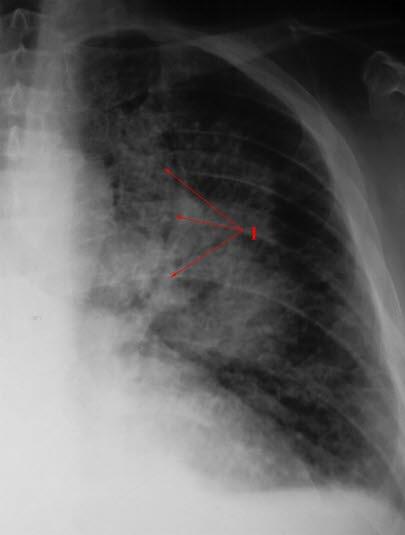

Diagnosen mistenkes på grunnlag av de typiske symptomene. Det vil bli tatt blodprøver for å kartlegge sykdommen, og røntgenundersøkelse av brystet er også aktuelt for å skille hjertesykdom fra lungesykdom med lignende plager. EKG viser oftest tegn til underliggende hjertesykdom. For bekreftelse av diagnosen er det nødvendig å foreta en ekkokardiografi,som er en ultralydundersøkelse av hjertet